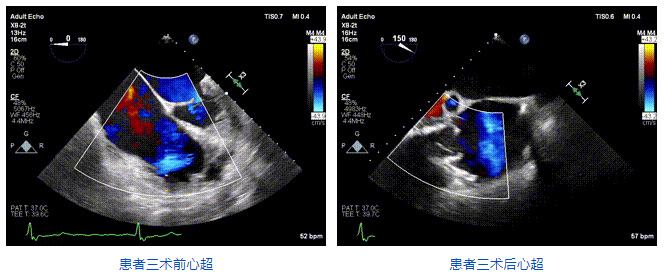

2021年12月24日,復(fù)旦大學(xué)附屬中山醫(yī)院葛均波院士團(tuán)隊(duì)成功應(yīng)用LuX-Valve Plus為一例極重度三尖瓣反流(TR)合并房顫、房缺的患者完成了經(jīng)血管三尖瓣置換術(shù),這是在前基礎(chǔ)上,本周完成的第三例經(jīng)血管三尖瓣置換手術(shù),葛均波院士、周達(dá)新教授等與心外科魏來教授、賴顥教授,心超室的潘翠珍教授、李偉教授及麻醉科的郭克芳教授共同完成了本周手術(shù),均獲得圓滿成功!患者術(shù)后超聲顯示無TR,臨床癥狀明顯改善。本周手術(shù)的成功也為L(zhǎng)uX-Valve Plus救治性臨床研究添上了濃墨重彩的一筆。

三例患者入院后,葛均波院士團(tuán)隊(duì)周達(dá)新教授、潘文志教授、張?jiān)床┦?、陳莎莎博士及心超室的潘翠珍教授、李偉教授?duì)患者的情況進(jìn)行詳細(xì)評(píng)估和討論,最終決定為三例患者選擇LuX-Valve Plus40mm、50mm和50mm型號(hào)的瓣膜進(jìn)行手術(shù)治療。手術(shù)后即刻拔除氣管插管,術(shù)后患者三尖瓣反流癥狀得到顯著改善,復(fù)查心超結(jié)果顯示人工三尖瓣瓣膜支架固定穩(wěn)定,瓣葉關(guān)閉形態(tài)未見異常,未見明顯反流。